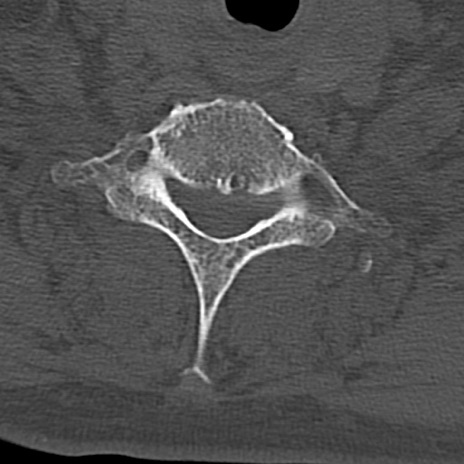

頚椎CT

横断像